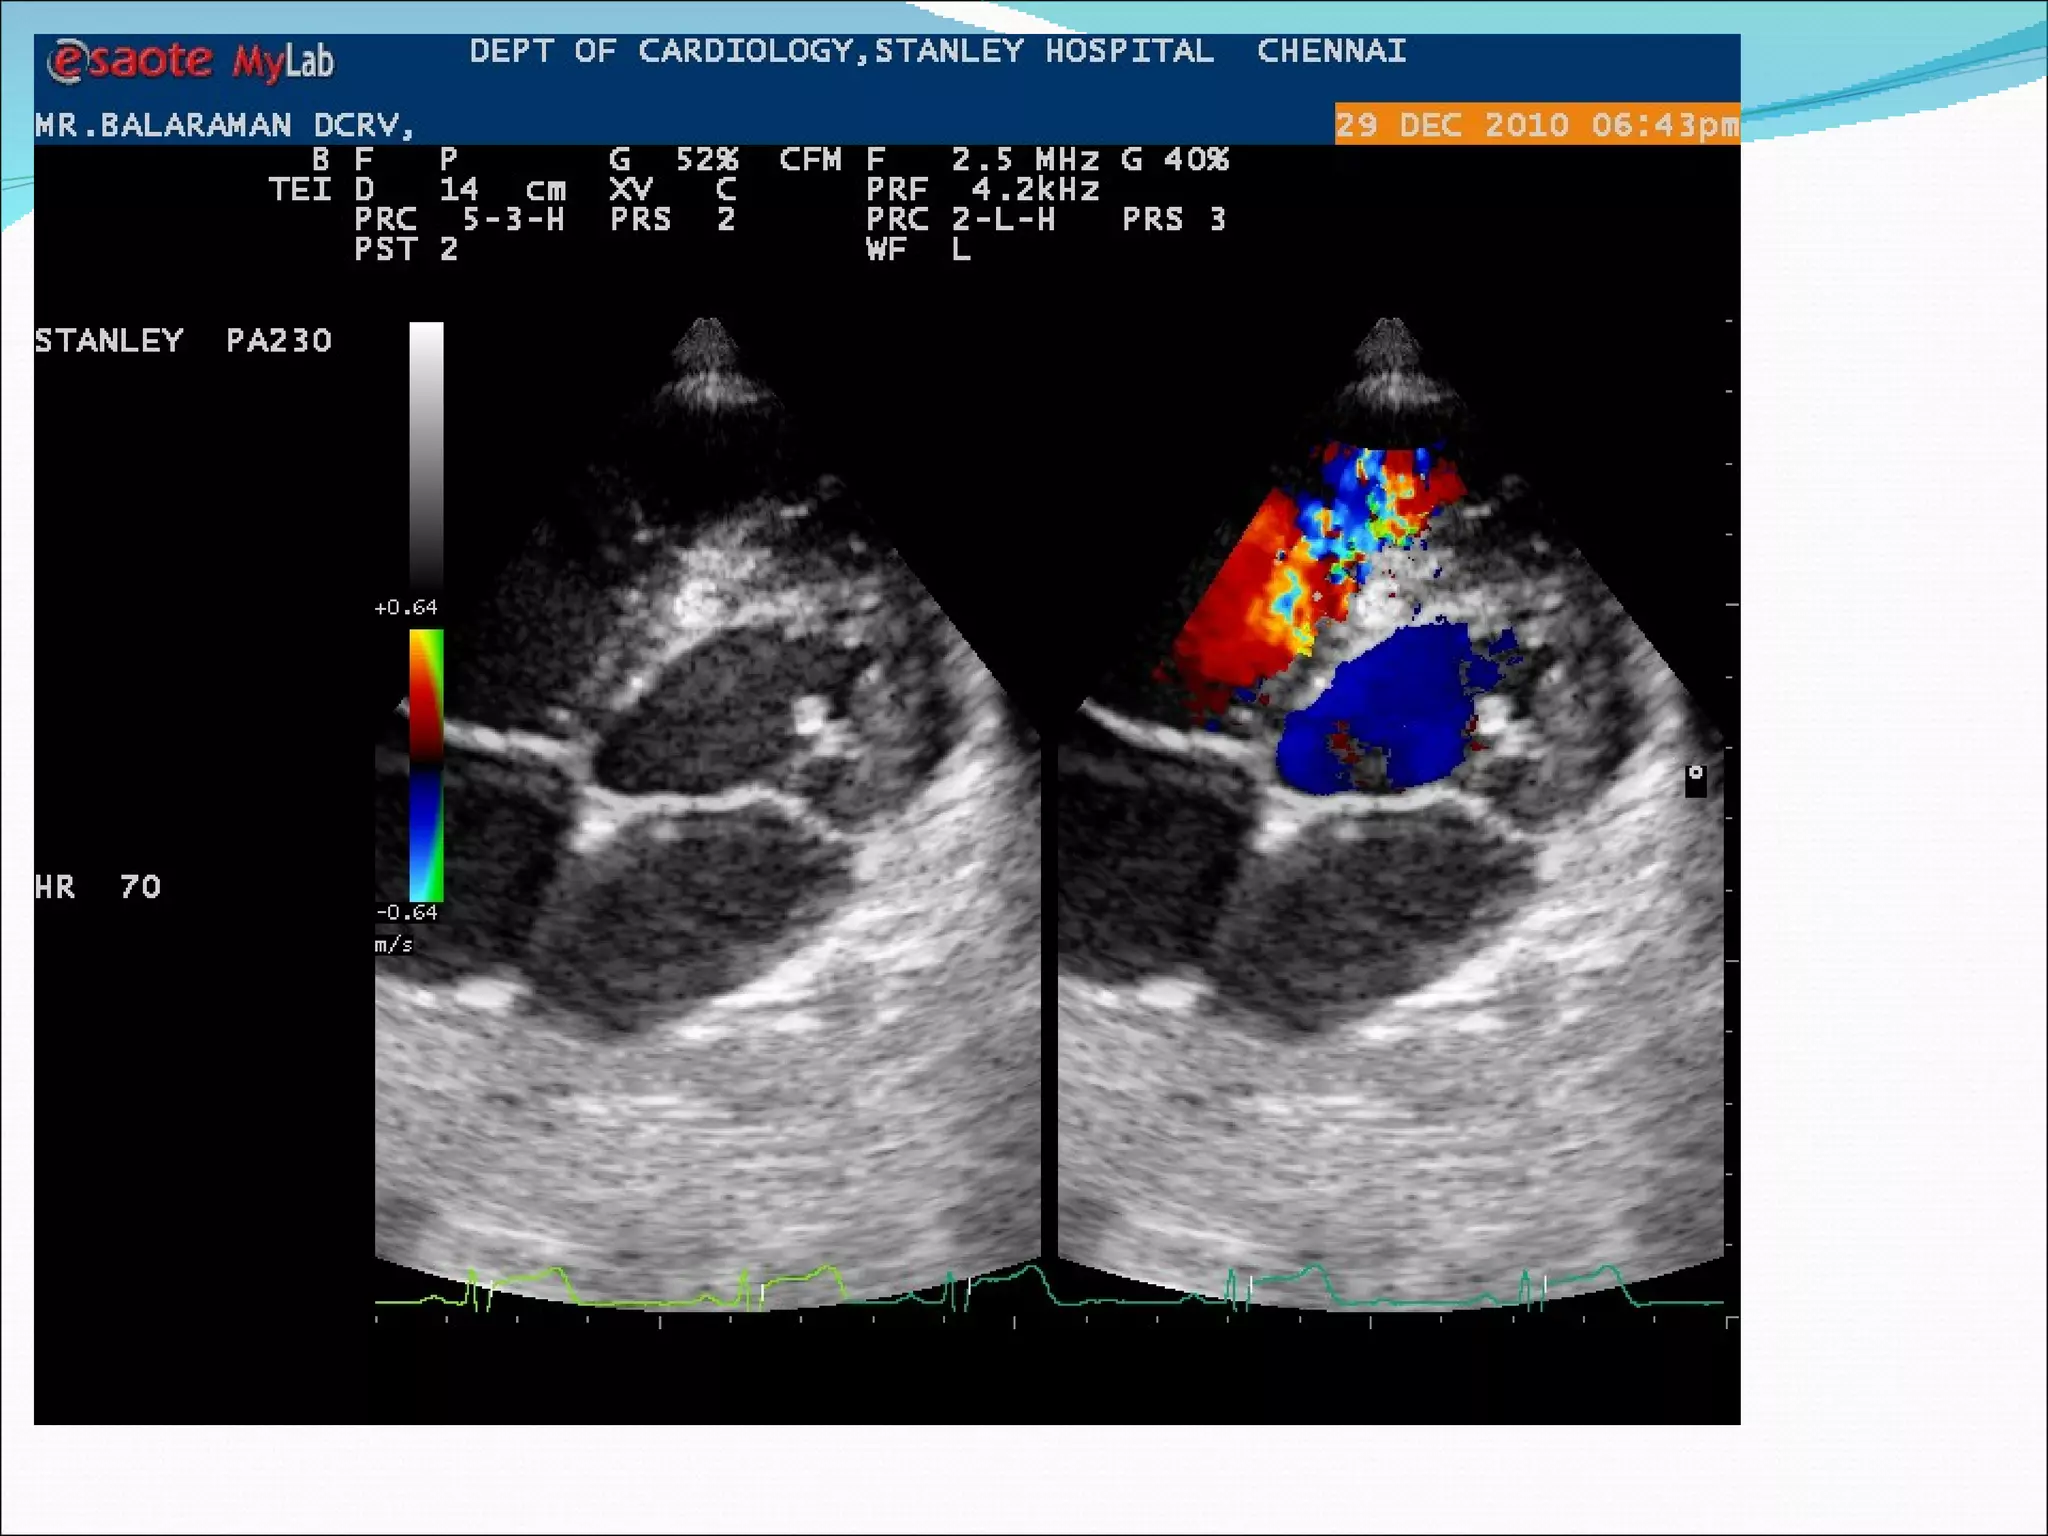

A 20-year-old male patient presented with complaints of palpitations and exertional breathlessness. On examination, he had a heart rate of 64 beats per minute, blood pressure of 100/70 mmHg, and a grade 5/6 pansystolic murmur heard best over the left parasternal area. An ECG showed right ventricular hypertrophy and right axis deviation. An echocardiogram confirmed the diagnoses of a ventricular septal defect and double chambered right ventricle.